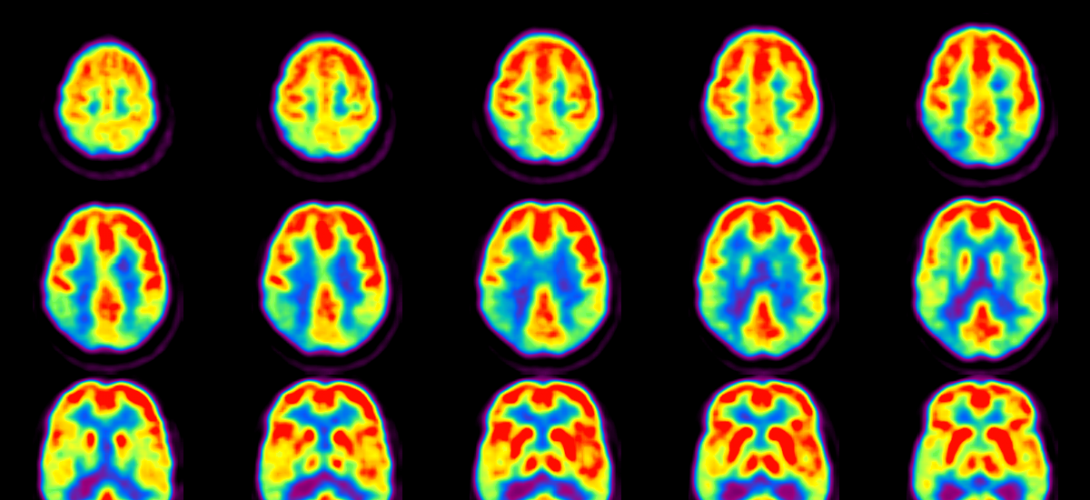

De nombreux examens ont été faits chez plusieurs enfants, (Electroencéphalogramme, Résonance Magnétique Cérébrale, PET-Scan, SPECT, Etude du caryotype, Recherches métaboliques…), aucun n’a donné de résultats significatifs jusqu’ici pour tenter d’expliquer la maladie.